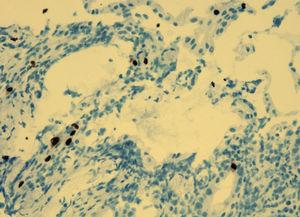

Durante el ingreso, la paciente desarrolló fiebre, dolor abdominal, vómitos y deposiciones diarreicas. Se realizaron coprocultivos, estudio de parásitos, determinación de toxina para Clostridium difficile y antigenemia para citomegalovirus (CMV) en dos ocasiones, que resultaron negativas. Se realizó TC abdominal (figura 1) en la que se observó engrosamiento de la pared del colon con oclusión de la luz desde el ciego hasta la unión recto-sigmoidea compatible con pancolitis difusa. Se solicitó fibrocolonoscopia (figura 2) en la que se objetivó una mucosa edematosa con múltiples lesiones nodulares blandas compatibles con neumatosis coli. En la biopsia de colon se detectaron inclusiones víricas que se confirmaron para CMV por inmunohistoquímica (figura 3). La tercera determinación de antigenemia para CMV fue positiva y el diagnóstico definitivo fue de colitis por CMV.

Figura 3. Biopsia de colon